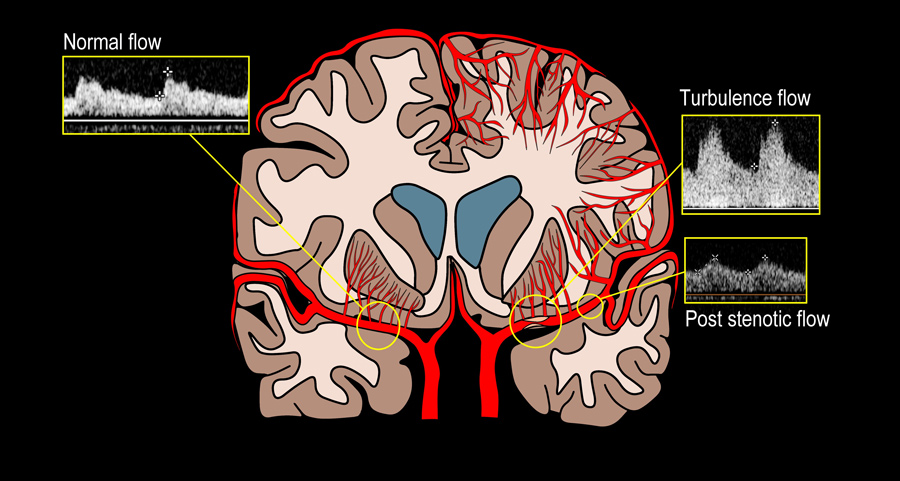

中风的原因有很多。增加患病可能性的因素包括高血压、糖尿病、吸烟、肥胖和急性感染等。一个更具体的原因是颅内动脉粥样硬化病(ICAD)。ICAD会导致大脑动脉疾病,即脂肪和胆固醇在动脉内堆积。这些淤积物,或斑块,是粘性物质,阻止血液到达以前供应充足的脑组织。通过这种方式使动脉变窄会导致血管逐渐减少血流,直到完全阻塞(颅内狭窄或闭塞),随后就会发生中风。如果斑块脱落并继续阻塞动脉的远端部分或分支(动脉到动脉栓塞),ICAD也会导致中风。ICAD可以在健康检查期间通过经颅多普勒或其他非侵入性成像方法检测到,但更常见的是在一个人已经中风后才确诊。

对245例患者进行了分析,发现ICAD病变处狭窄后低压力和高壁剪切应力与一年内再次中风的风险增加相关。简单地说,这些特征减少了流向脑组织的流量,对斑块施加了更大的压力,从而增加了进一步中风的机会。为了进一步研究ICAD,研究组使用了磁共振成像/计算机断层血管造影。这些脑成像技术使研究小组能够看到153名因ICAD而中风的患者的大脑和大脑中的血管。这种方法被用来识别中风机制,即动脉到动脉栓塞(流动的血凝块会阻塞血管)和低灌注(流向脑组织的流量减少)与一年之内复发风险增加(即第二次中风)有关。